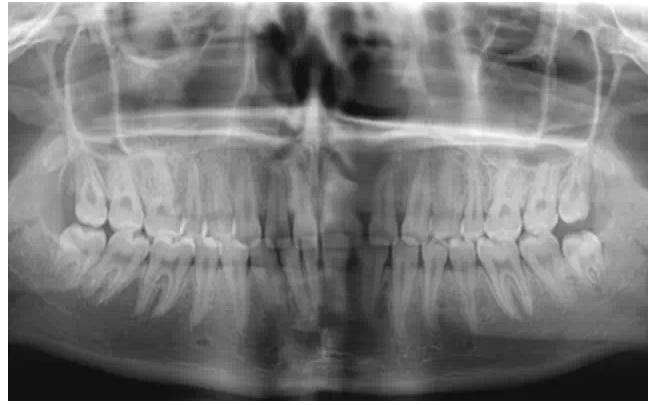

2、拍攝x線片

在修復(fù)前要判斷患者的牙周情況和牙齒的治療情況,做到知己知彼,為成功修復(fù)打下良好基礎(chǔ)。

曾有一個這樣深刻的教訓,患者因為前牙有縫,想做貼面修復(fù),剛做完的效果是很好的,可是過了半年,牙齒又出現(xiàn)了縫隙,通過x線片的檢查發(fā)現(xiàn),牙槽骨的吸收比較嚴重。所以,一定要對患者的牙周情況進行充分的把握。